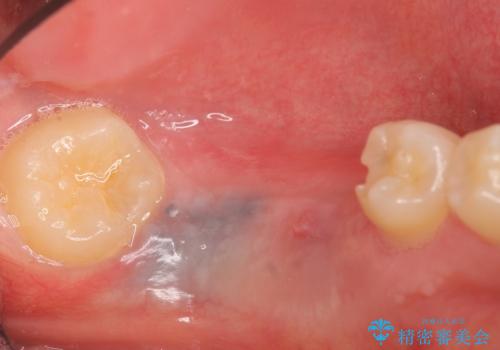

- 数年前に左下の奥歯を2本失ってから物が咬めないため何とかして欲しいと当院にいらっしゃった方の症例です。

左下にインプラント(ストローマン)を2本埋入し、オールセラミッククラウンによる補綴を行いました。